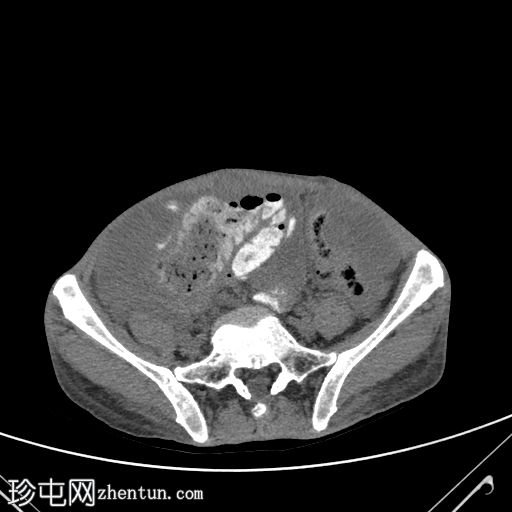

直肠穹窿可见一处厚度 1.2 cm、长 4.0 cm 的增强壁增厚。可见病灶周围及骶前淋巴结肿大,最大者直径 1.6 cm。

左下腹可见末端结肠造口。

大网膜和肠系膜内可见低密度、不均匀的腹膜积液,脏器表面呈扇形凹陷,尤其以肝脏和脾脏最为明显。